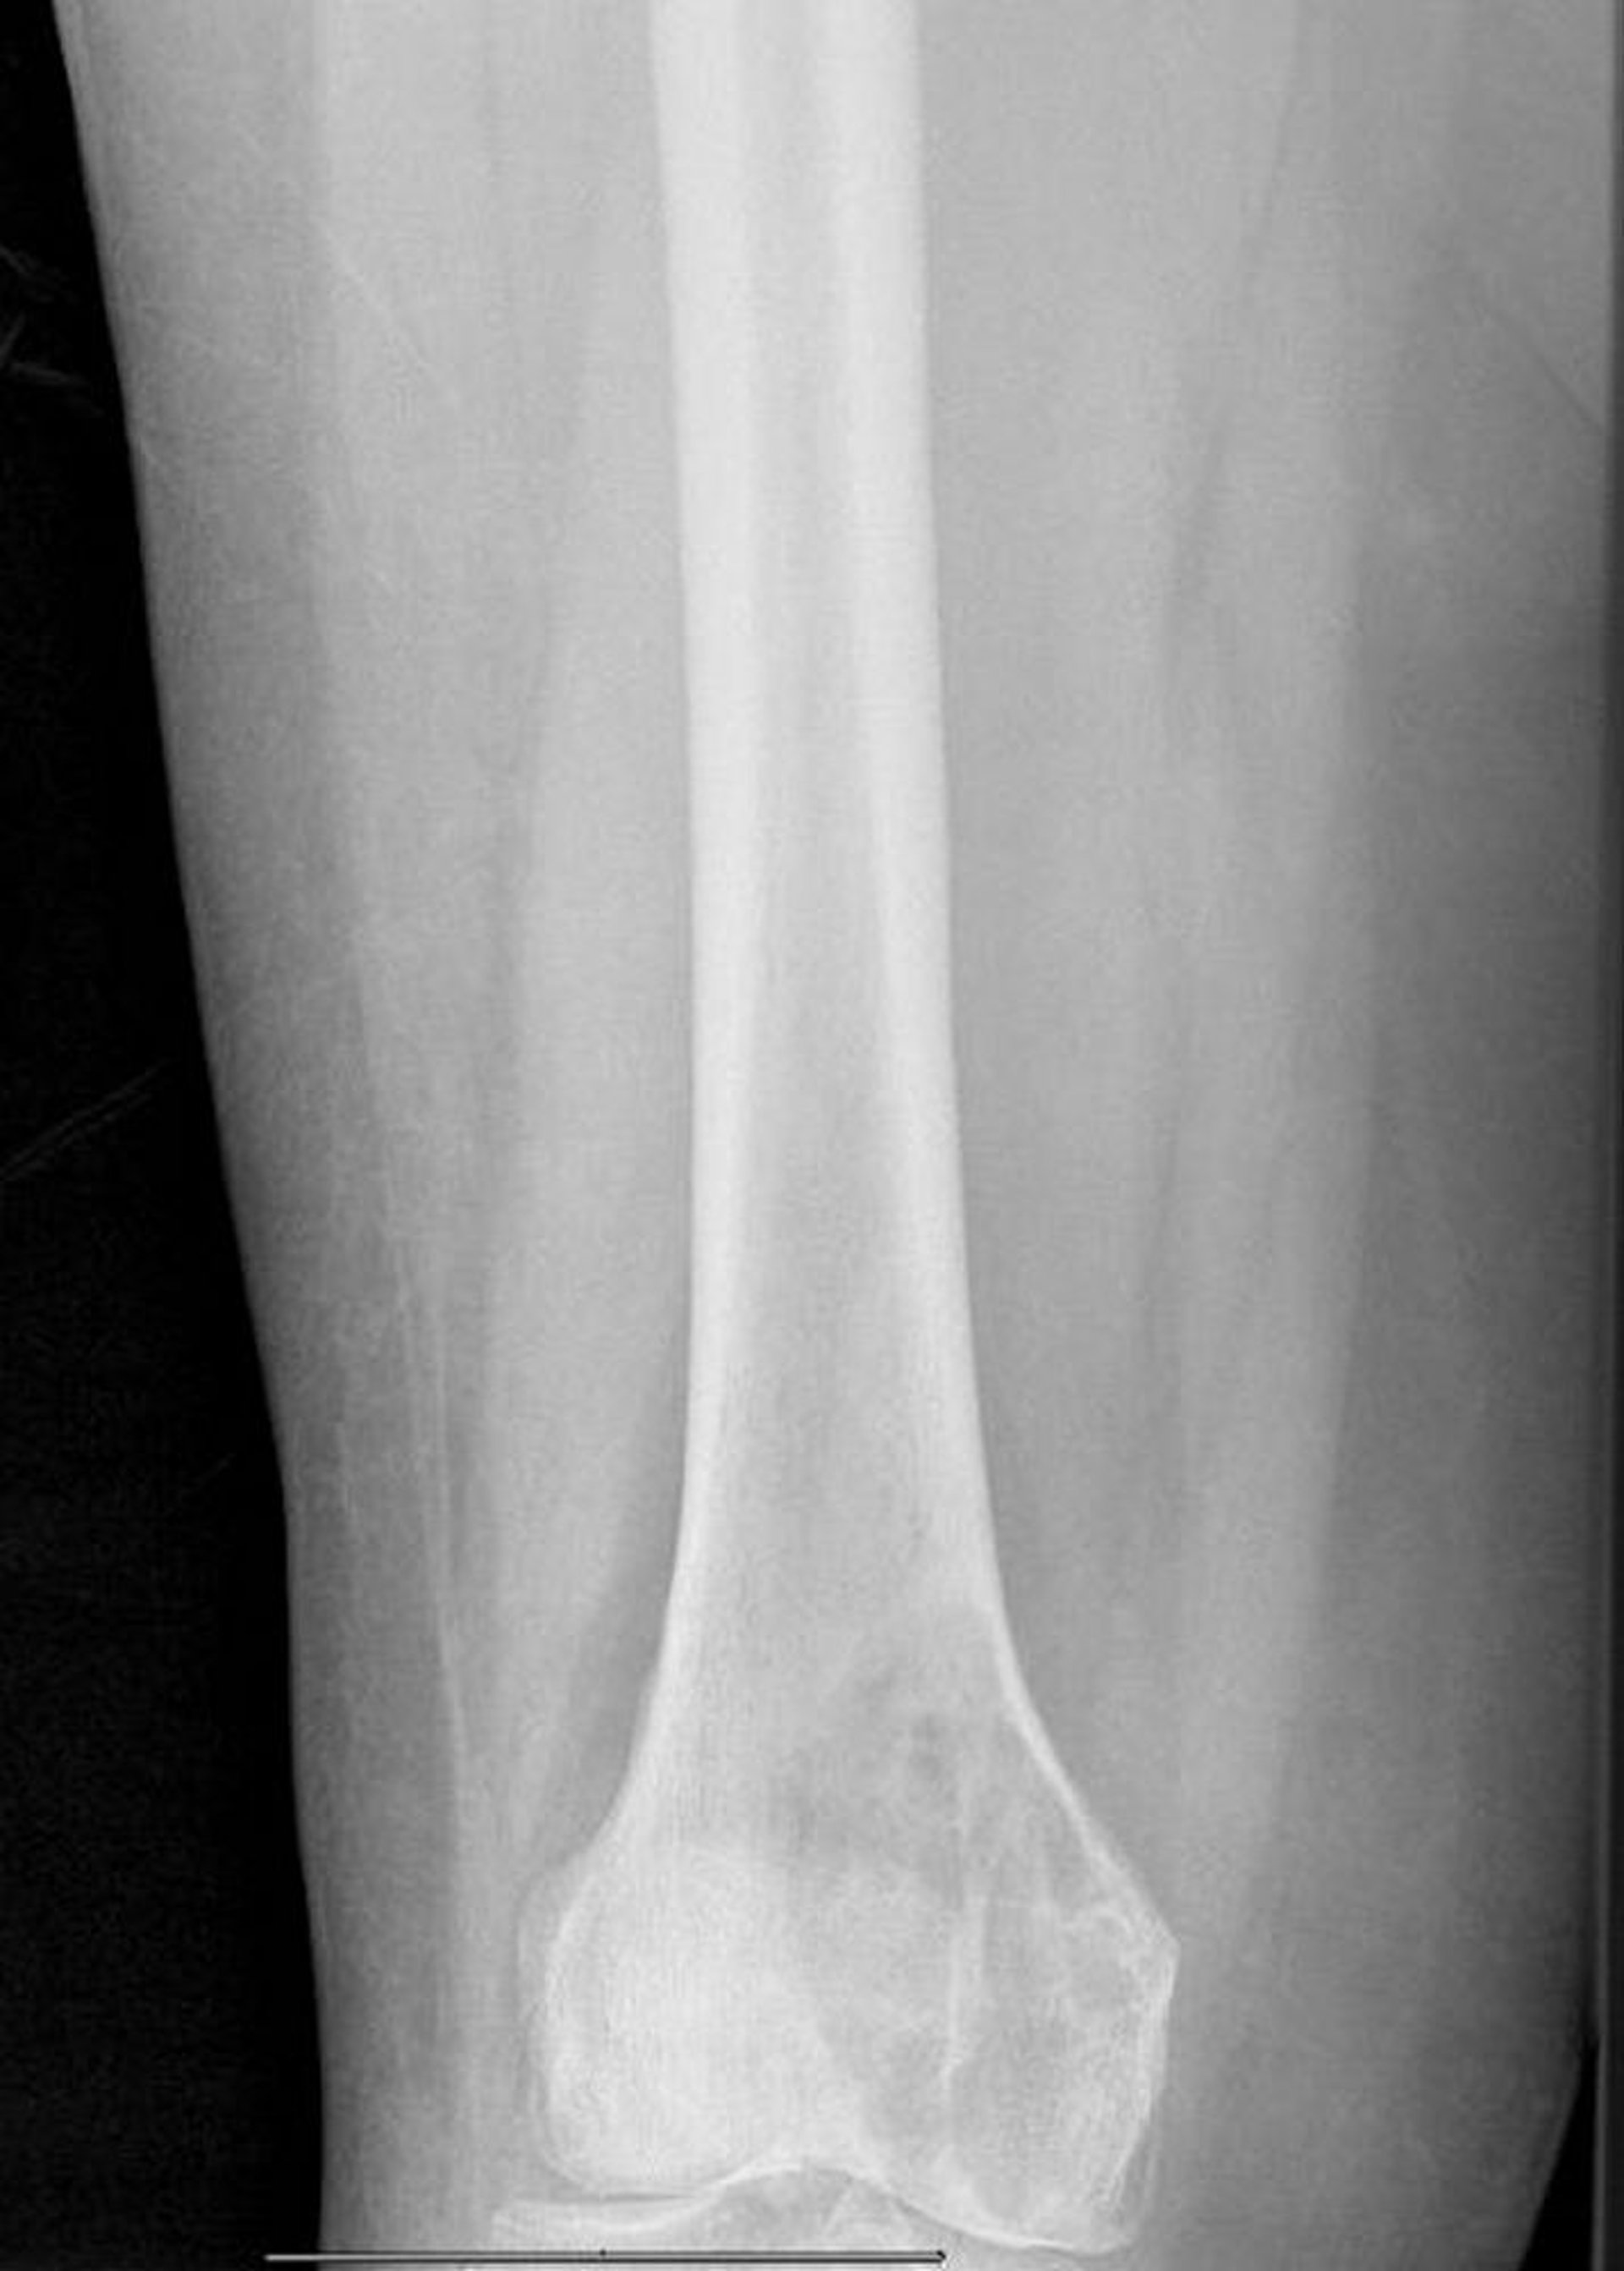

Metástasis líticas en el fémur distal

Esta radiografía muestra una gran lesión lítica metastásica del cóndilo medial del fémur con fractura patológica inminente.

Image courtesy of Michael J. Joyce, MD, and David M. Joyce, MD.